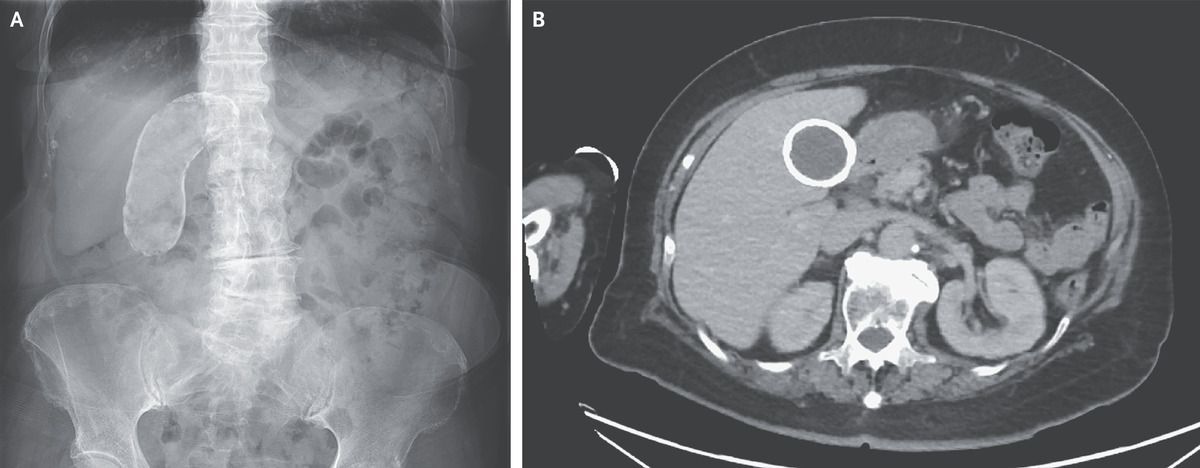

An 83-year-old woman presented to the outpatient clinic with nausea. At the time of presentation, she was receiving antibiotic treatment for cellulitis, and her condition was improving. Her medical history was also notable for an episode of biliary colic when she was 40 years of age. Results of the physical examination, including the abdominal examination, were unremarkable. A plain radiograph of the abdomen showed gallbladder calcification (Panel A), and a computed tomographic scan showed multiple calcified gallstones, as well as rim calcification of the gallbladder (Panel B), a finding consistent with porcelain gallbladder. Porcelain gallbladder refers to the calcification of the gallbladder wall and is associated with chronic gallbladder inflammation. Although porcelain gallbladder is associated with an increased risk of gallbladder carcinoma, the role of prophylactic cholecystectomy in the treatment of asymptomatic patients has not been definitively established. The nausea, which may have been related to the antibiotic treatment, resolved without further intervention. Since this patient did not have ongoing symptoms of gallbladder disease, her condition was managed without surgery. She has attended regular clinic follow-up visits and has not had further episodes of biliary colic or other abdominal symptoms.